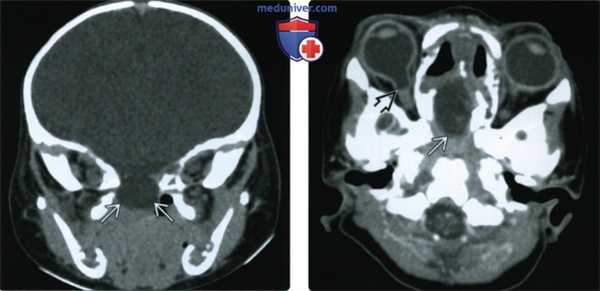

(Слева) МРТ, постконтрастное Т1-ВИ, режим подавления сигнала от жира, сагиттальный срез: крупное цефалоцеле, выходящее через крупный срединный дефект клиновидной кости и содержащее СМЖ и мозговые оболочки. Зрительный перекрест подтянут, зрительные нервы растянуты, наблюдается компрессия гипофиза.

(Справа) МРТ, Т2-ВИ, аксиальный срез: по срединной линии перед клиновидно-затылочным синхондрозом визуализируется гиперинтенсивная зона, которая оказалась срединным клиновидным цефалоцеле. (Слева) МРТ, Т2-ВИ, аксиальный срез (лобно-носовое переднего -ловное цефалоцеле): грыжевое выпячивание головного мозга через крупный костный дефект в области соединения лобной и носовой костей. Отмечается неоднородность интенсивности сигнала от диспластичной выпяченной ткани головного мозга и ее легкое повышение относительно нормальной мозговой паренхимы.

(Справа) КТ, костный режим, корональная 3D-реконструкция (лобно-носовое переднеголовное цефалоцеле): визуализируется крупный костный дефект в срединных отделах, коррелирующий с аномально широким передним родничком.